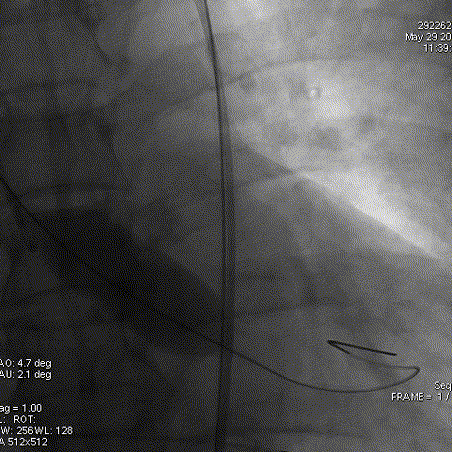

主动脉根部造影

工作位造影